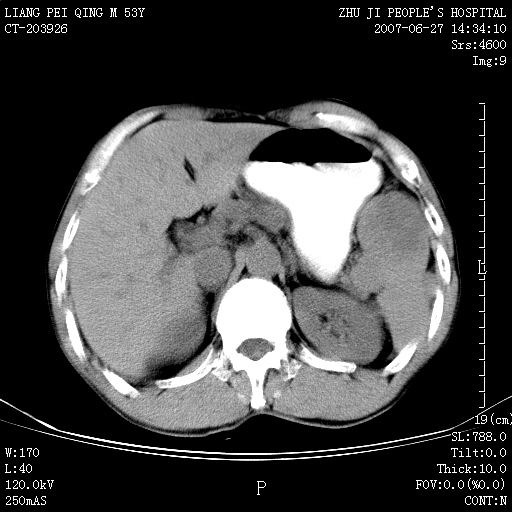

以下是引用余辉在2007-6-27 18:46:00的发言:[br]病灶多发,内可见大片状低密度区,病灶病灶等密度区轻度强化,动脉期后期病灶低密度区与高密度区对度增加,考虑1淋巴瘤2转移瘤3血管内皮细胞瘤(不知有否静脉期及延迟期扫描)

以下是引用zzzzhhhhaaaannnn在2007-6-27 20:44:00的发言:[br]脾脏 肋骨转移可能性大,下腔静脉内有癌栓

以下是引用狙击手在2007-6-28 10:35:00的发言:[br]1:定位:来源于脾脏。2:强化:强化,但不均匀。3:下腔静脉癌栓?下腔静脉充填不均匀与增强时间有关,延时即可明确。4:肋骨破坏?看起来并不确切。综上考虑几个最常见诊断:1;淋巴管瘤;2;血管内皮肉瘤(高度恶性,早期即可转移,常见肝,肺,骨)3;转移瘤(无特征性,只有肝或其它腹腔脏器有类似病变时,才可提示之)